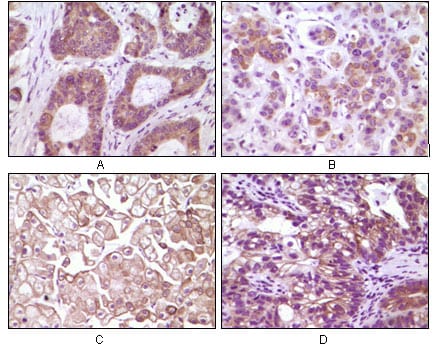

分类: 科研抗体货号: 20074别名: SRAP; STRAA1应用: IHC反应种属: Human

分类: 科研抗体货号: 20075别名: SRAP; STRAA1应用: IHC反应种属: Human